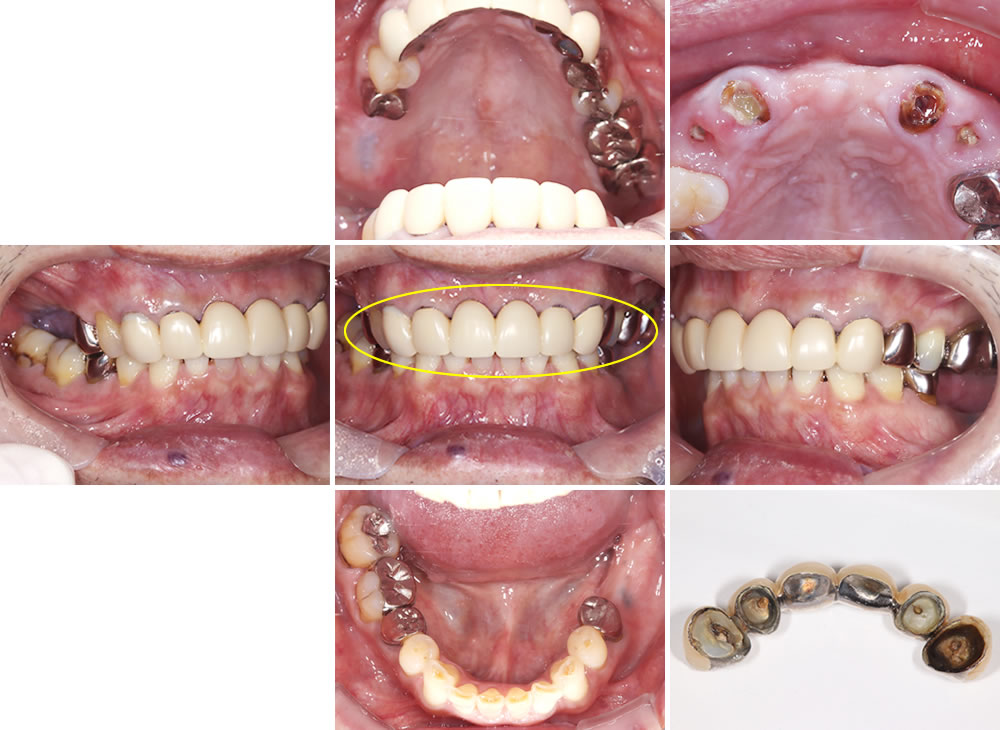

こちらの患者さまは、上顎前歯部分の差し歯が取れたとのことで初診来院されました。右下の写真からもわかるように、補綴物が広範囲にわたって脱離していることが確認できます。

採取した型を基に制作した最終的な上部構造(人工歯)です。